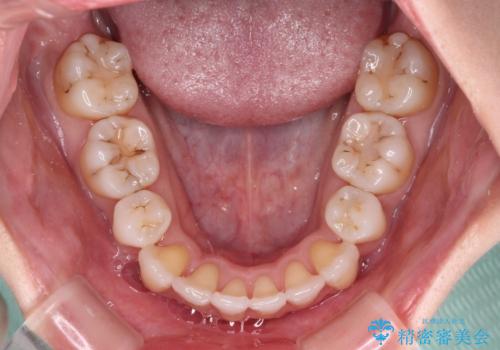

- 結婚式に向けて、八重歯と虫歯で変色した歯を改善したいとのことで来院された患者様です。

上下ともにデコボコが強いため、上下顎左右小臼歯各1歯を抜歯して歯列を整えることとしました。

大きな虫歯が認められた歯は、矯正治療後にオールセラミッククラウンにて補綴治療を行うこととしました。

抜歯矯正は、2年半程度の治療期間を要することが一般的ですが、今回はセラミッククラウンによる補綴治療も含めて2年1ヶ月で終えることができました。

元々の歯並びが思い出せないくらい、きれいに仕上げることができました。